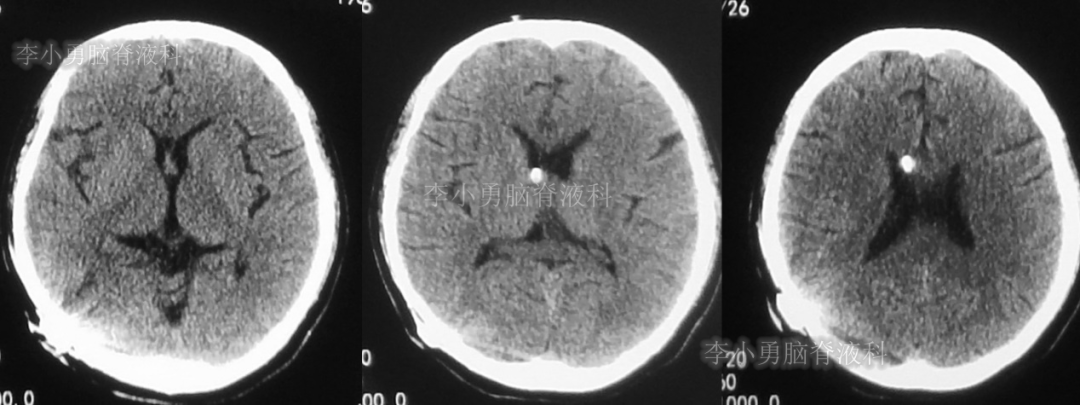

图-4:2018年11月10日头颅CT

次日,即2018年11月11日,患者第2次到给予脑室腹腔分流术的医院,复查头颅CT(图-5)见脑积水仍严重。

图-5:2018年11月11日头颅CT

但第2次调压后2周,即2018年11月28日,再次到当地的第1家医院复查头颅CT(图-6)见脑积水缓解。

图-6:2018年11月28日头颅CT